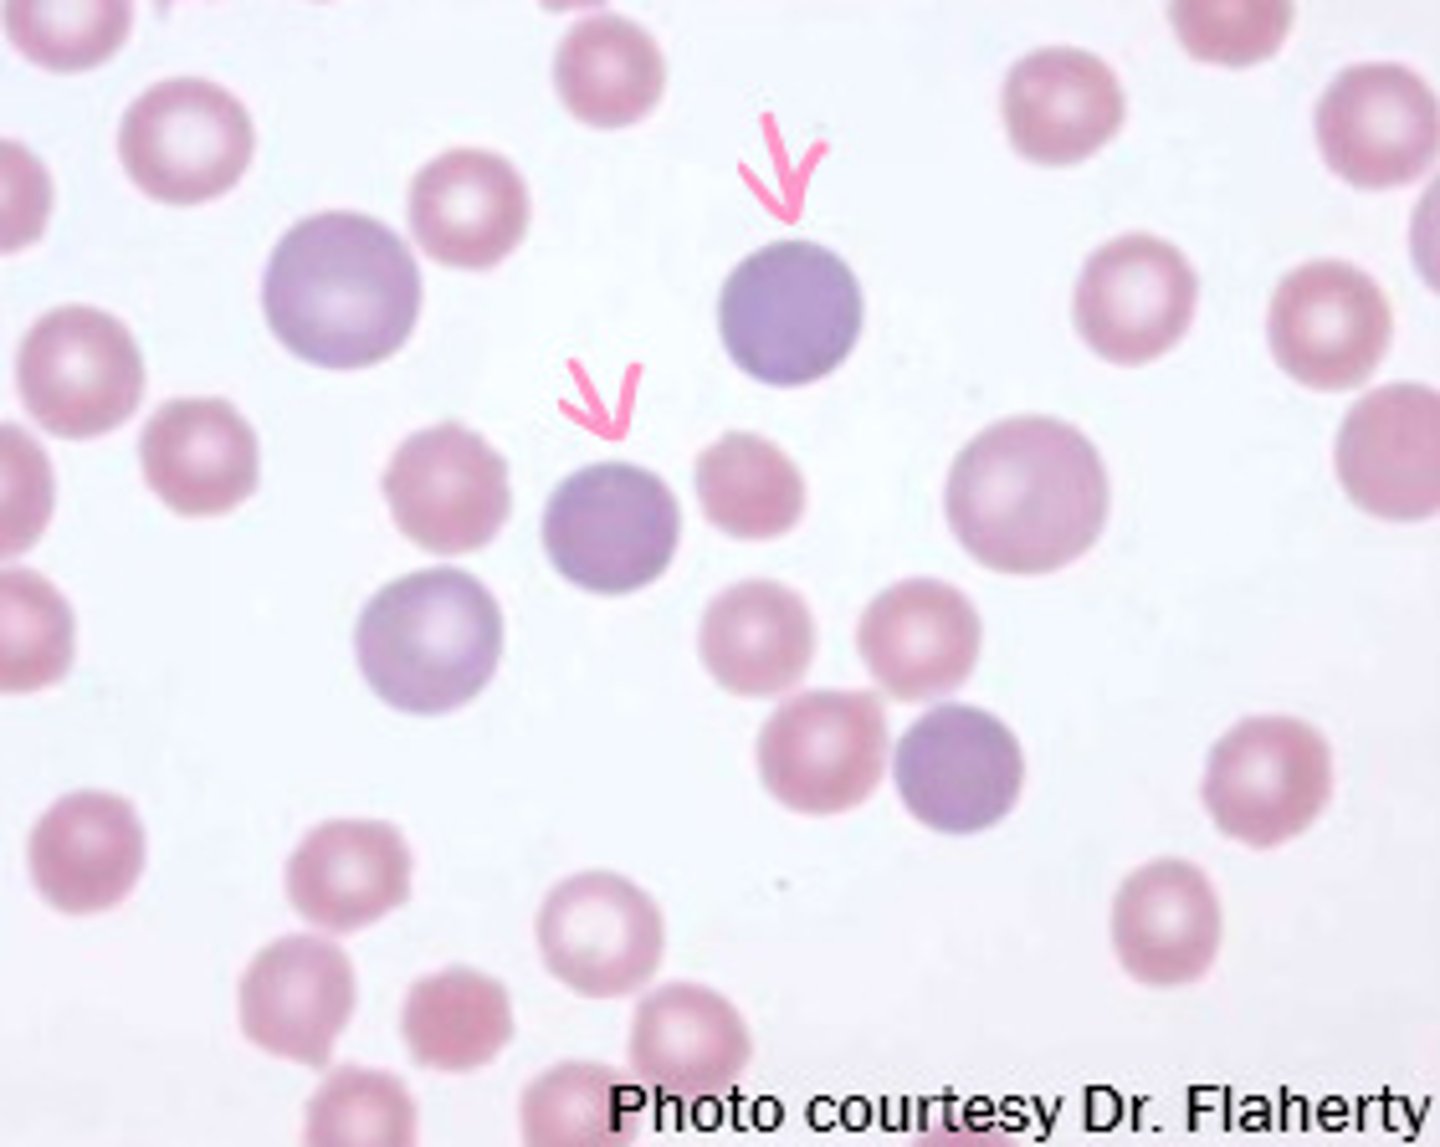

polychromasia

MAMMAL

residual RNA in cytoplasm stains the cell bluish

**reticulocytes when stained with NMB

- not in equine

anisocytosis

MAMMAL

mixture of mature and immature RBCs

- variation in RBC size

aggregate reticulocytes

orange arrow

hint: NMB stain

punctate reticulocytes

**not counted

green arrow